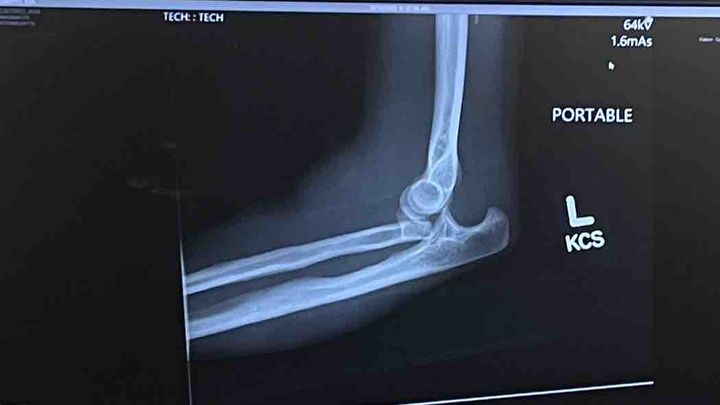

This past weekend I broke and dislocated my left elbow as well as tore a bunch if ligaments.